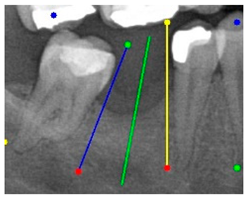

The angle bisector of the two auxiliary lines was then calculated using the angle bisector formula shown in (8), where (, , ) and (, , ) represent the coefficients of the two lines. The resulting internal angle bisector defines the preliminary implant pathway orientation derived by this framework. This bisector represents the most stable implant pathway orientation direction, ensuring that the implant avoids adjacent teeth and critical anatomical structures while maximizing bone–implant contact area. Such orientation enhances osseointegration stability and prevents complications from improper angulation, such as malocclusion or uneven stress distribution. The visualization of this process and the algorithmic design are presented in Figure 8. Finally, the auxiliary pathway generated by the algorithm was compared and overlapped with the implant pathway orientation annotated by dentists on the images to evaluate the predictive capability and accuracy of the model. The overlap results serve as a basis for further model optimization and provide valuable reference information for clinical application.

Figure 8.

Auxiliary lines are derived from adjacent teeth, the blue and yellow line is the result of implant pathway orientation visualization algorithm, and the green is the best implant pathway orientation.

3.3. Comparison with Clinical Ground Truth and AI-Assisted Framework

This subsection presents a comparison between the dentist-defined clinical gold standard and the predictions generated by our AI-assisted framework to evaluate the reliability of implant pathway orientation. The result is shown in Table 10, the preserved DPR validation set was used for verification, and the AI-assisted framework results were overlaid onto the original DPR images to provide a clear visualization. The AI-assisted framework pathways (green lines) were highly consistent with the dentists’ ground-truth annotations (black lines). Quantitatively, the mean squared error (MSE) between the predicted implant direction and the dentists’ planned results was only 1.537° across multiple test images. This minimal deviation validates the proposed system’s technical feasibility. It highlights its clinical potential to provide accurate and stable guidance for implant placement, thereby reducing the risk of misalignment and supporting efficient preoperative orientation.